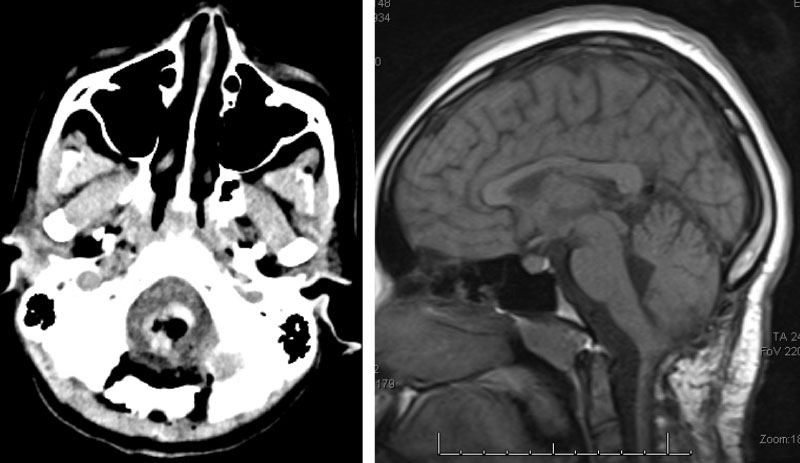

A pre-surgical cerebral angiogram was performed to investigate the vascular lesion and to attempt pre-operative embolization (Figure 2). A hypervascular posterior fossa tumor mass was confirmed with major vascular supply from the anterior spinal artery. The attempts for pre-surgical embolization were difficult (anterior spinal artery access) and had to be aborted.

Figure 2. Posterior circulation cerebral angiogram. Right vertebral artery (R-VA) injection, mid- and late-arterial phase (A, B) and left VA injection mid- and late-arterial phase (C, D) showing filling of a vascular tumor mass (TM) fed by the anterior spinal artery (ASA). Basilar artery (BA).